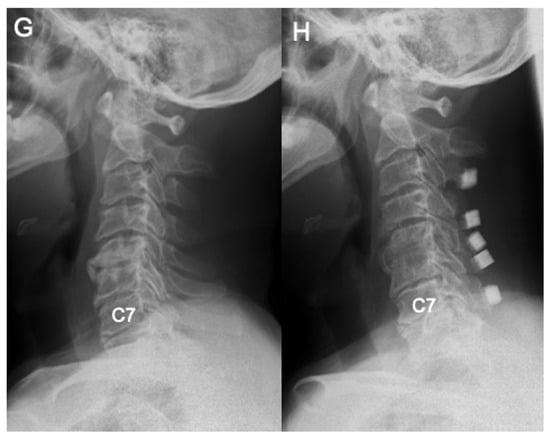

Differences in Demographic and Radiographic Characteristics between Patients with Visible and Invisible T1 Slopes on Lateral Cervical Radiographic Images

- Park, B.J.; Gold, C.J.; Woodroffe, R.W.; Yamaguchi, S. What is the most accurate substitute for an invisible T1 slope in cervical radiographs? A comparative study of a novel method with previously reported substitutes. J. Neurosurg. Spine 2021, 1, 1–7. [Google Scholar] [CrossRef] [PubMed]

- Tamai, K.; Buser, Z.; Paholpak, P.; Sessumpun, K.; Nakamura, H.; Wang, J.C. Can C7 Slope Substitute the T1 slope?: An Analysis Using Cervical Radiographs and Kinematic MRIs. Spine 2018, 43, 520–525. [Google Scholar] [CrossRef]